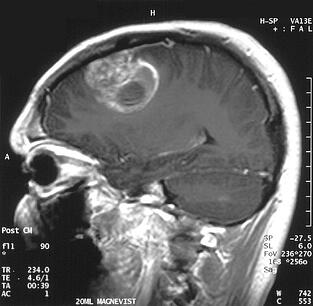

(image of glioblastoma tumor courtesy of Christaras A on Wikipedia commons)

Chemotherapy always produces negative side effects in cancer patients. However, in the case of the glioblastoma brain cancer these effects are particularly severe. Glioblastoma is a terminal form of brain cancer with no known curative treatment. The median survival time for patients diagnosed with glioblastoma is just 12 to 15 months. This is in part due to the relative ineffectiveness of the best available treatment, chemotherapy.